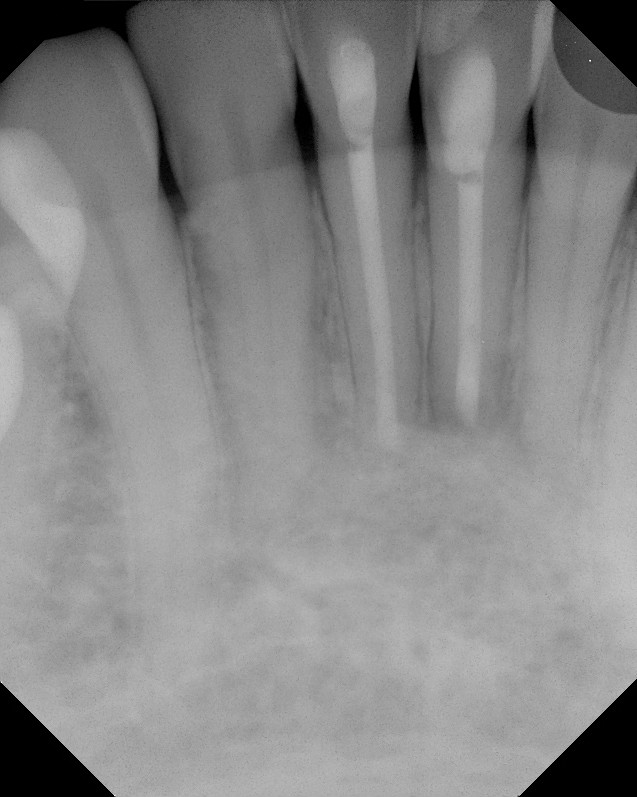

Endodontic Surgery Explained Riverbend Endodontics

The Endo Blog Success with endodontic surgery (apicoectomy) Endodontic Apicoectomy The renowned specialist also sheds light on the success rates of apicoectomy surgery and how the use of advanced surgical techniques and technology. during an apicoectomy operation, your endodontist removes the tip of the tooth’s root (otherwise known as the apex). an apicoectomy is a common dental procedure where inflamed gum tissue and the end of the root. Endodontic Apicoectomy.

From www.theendoblog.com